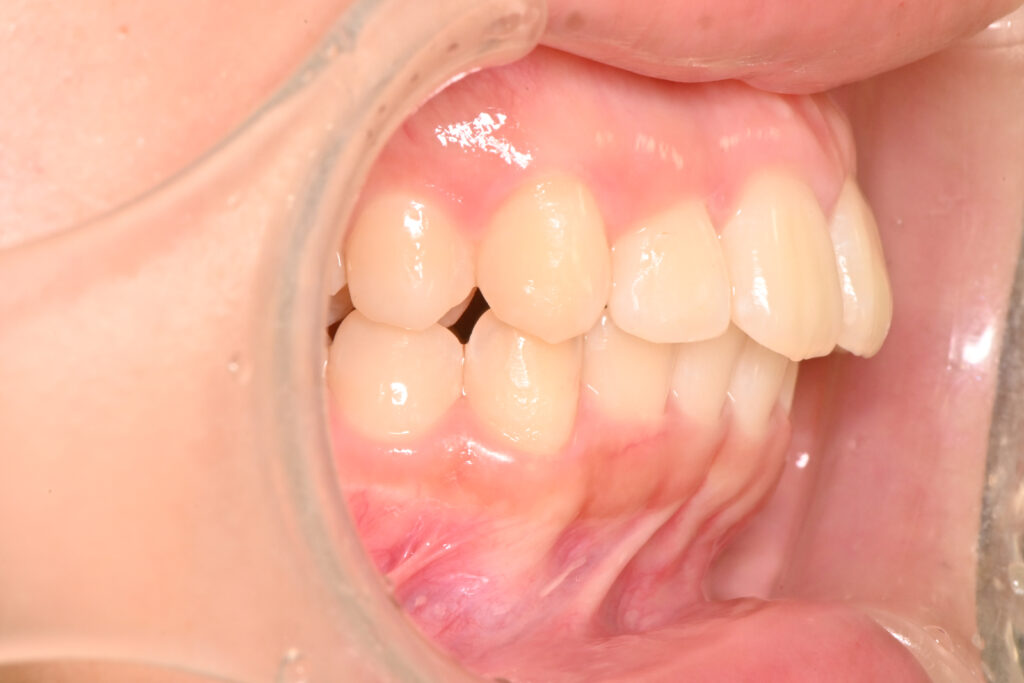

オーバージェット

治療前

治療後